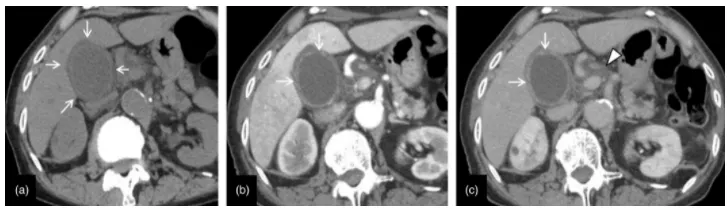

괴사성 담낭염의 전형적인 컴퓨터 단층촬영(CT) 이미지. 70대 여성, 괴사성 담낭염(급성 비결석성 담낭염). 동적 조영증강 CT (a, 일반; b, 초기 단계; c, 평형 단계). 일반 CT에서 담낭의 확대, 담낭 벽의 두꺼워짐, 담낭 장막 아래의 부종성 병변이 나타납니다(화살표). 조영증강 CT (b, c)에서는 담낭 벽의 불규칙성과 부분적인 조영 증강 부족이 보이며(화살표) 이것이 괴사성 담낭염의 특징적인 소견입니다. 초기 단계에서 간 실질의 일시적인 염색 (b)과 간십이지장 인대의 부종성 변화 (c, 화살표)가 나타나며, 이는 염증의 확산을 시사합니다.